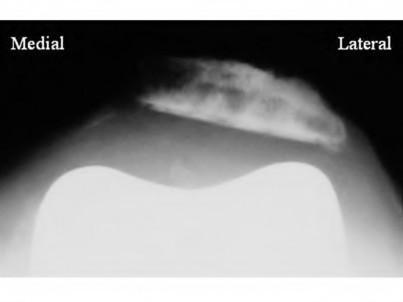

Question 1:

A 32-year-old female presents with knee pain. Radiographs show an eccentric, lytic epiphyseal lesion. Biopsy shows multinucleated giant cells and mononuclear stromal cells. Denosumab therapy is considered. What is the precise mechanism of action of Denosumab?

Correct Answer: Binds to RANKL, preventing interaction with RANK

Explanation:

Denosumab is a monoclonal antibody that specifically binds to RANKL (Receptor Activator of Nuclear factor Kappa-B Ligand). By binding to RANKL, it prevents it from interacting with the RANK receptor on the surface of osteoclasts and giant cells, thereby profoundly inhibiting osteoclastogenesis and tumor-associated bone lysis in giant cell tumors.